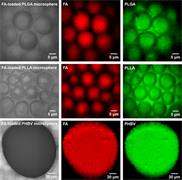

- Identify and differentiate API polymorphs and excipients

- Generate images of the formulations used in tablets, inhalers and nasal sprays at sub-micrometre spatial resolution

- Analyse API and metabolites in cells and tissue